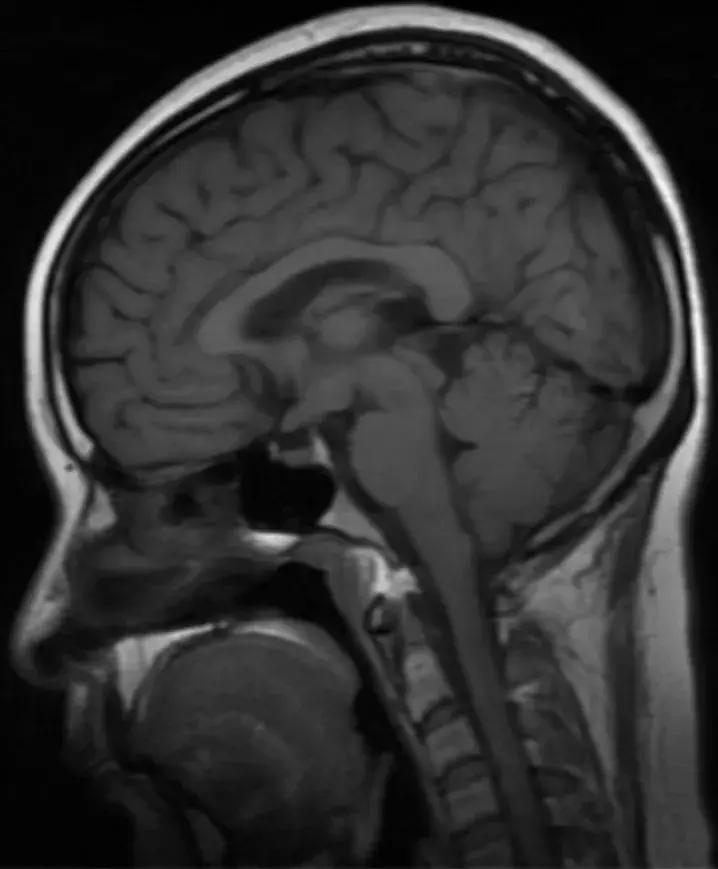

下丘脑见一类圆形异常信号灶,大小约1.6×1.4cm,T2WI呈等略高信号,T1WI呈等信号,DWI呈等信号,增强后明显异常强化,轻度压迫视交叉,FLAR见视交叉及双侧后方视束信号增高。